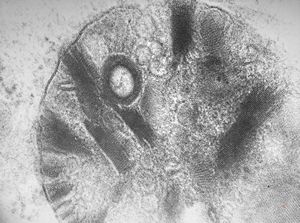

M,22y. | type II membranoproliferative glomerulonephritis